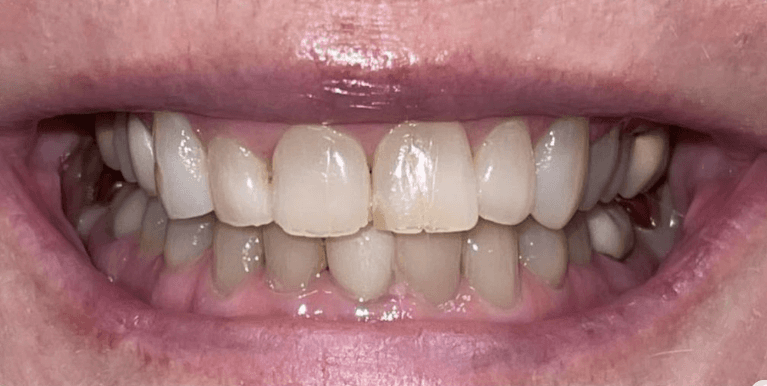

Smiles are always in fashion because the prettiest thing you can wear is a smile (maybe mask for a time being ) Before and after pictures of 4 porcelain veneers.

Smiles are always in fashion because the prettiest thing you can wear is a smile (maybe mask nowadays) Before and after pictures of yesterday’s case. Slight gum bleeding was from flossing..no biggie